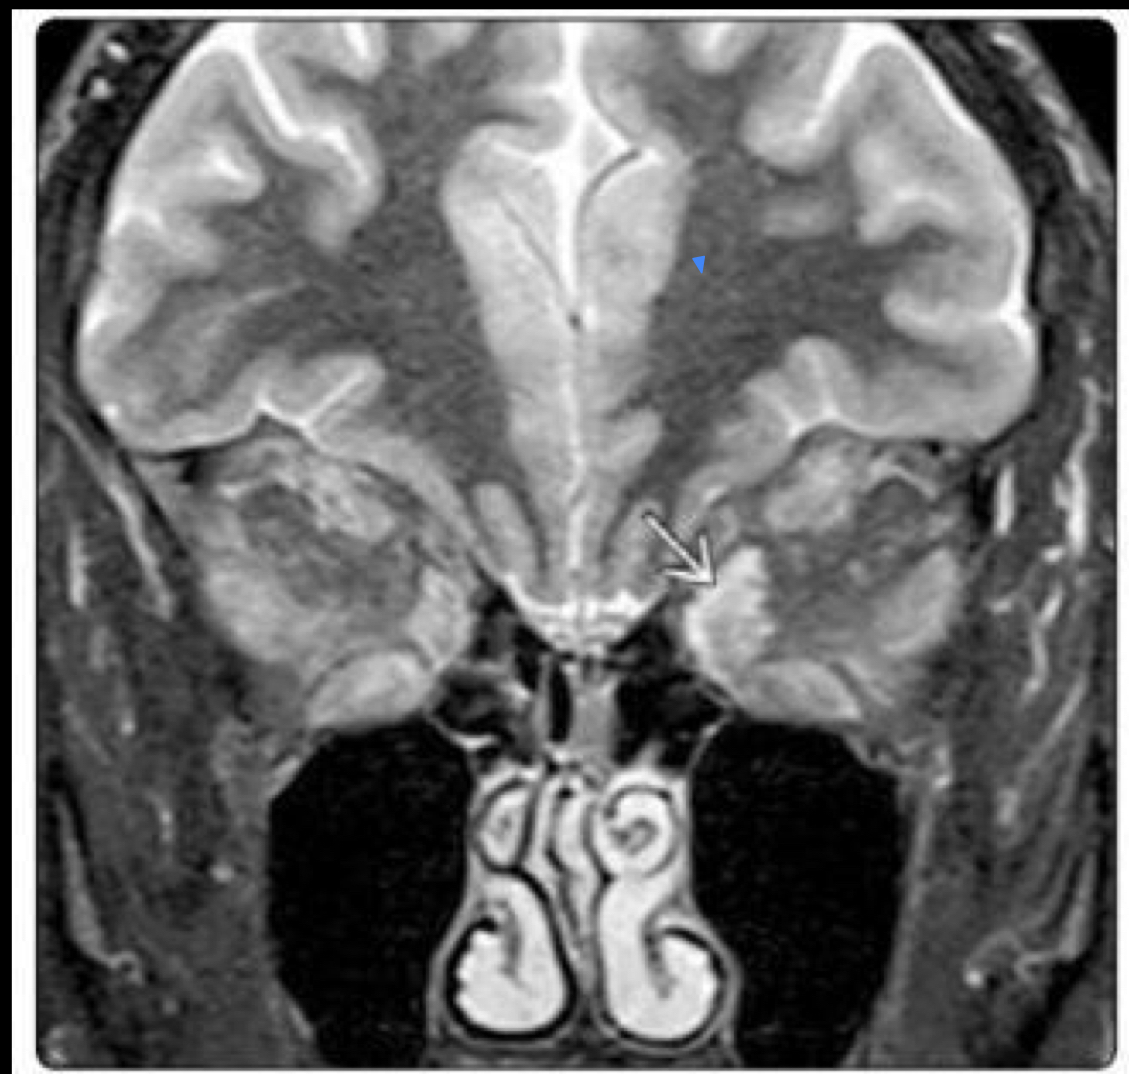

9

Q

Que es?

A

Tc EXOFTALMOS

* protusion ocular anormal

* disociasion indice globo ocular-linea zigomatica

* Masa Ocupativas retrooculares

13

Que se obsevra?

Tc Retinoblastoma trilateral

* Calcificación en ojo

* Capta contraste

* Tumor pineal